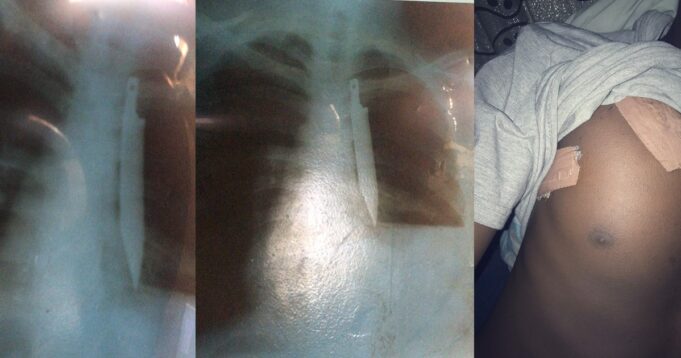

Harry said his health always suffered constant relapses and he was advised to go for an X-ray where he discovered the piece of metal was still dwelling inside his chest.

But after the stabbing incident, my health went from 100-10. I fall ill every 2wks from one medication to another no proper improvement, so we had to go see our family doc, who advised us to go for an X-ray after carrying out some checkup on me, low and behold “ A knife “

A knife inside my chest?? How come? Shebi that doctor that stitched me up said the wounds weren’t that deep and I was very lucky? So Where the knife pass enter my body go digest for my chest??. To make things worst family doc said the only way out was an operation. My hrt skip

Not to take anything away from the doctors that carried out the operation, they really did their maximum for me, professionals wey sabi work. God bless all UBTH professionals